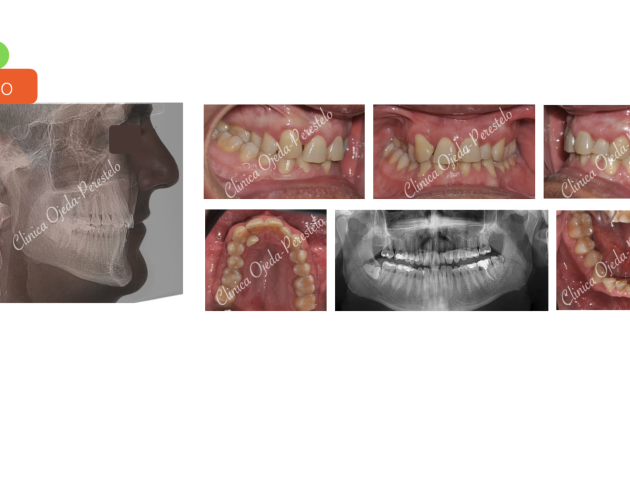

Casos de Éxito